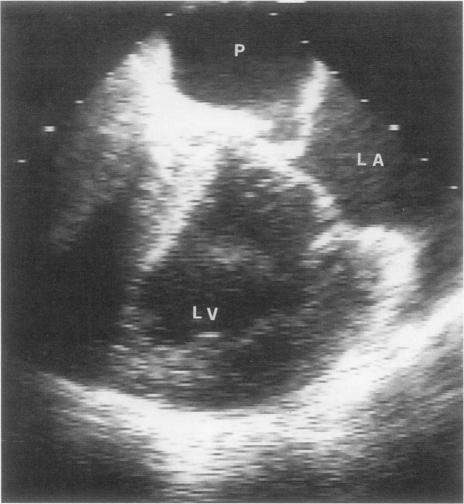

Pseudoaneurysms of the left ventricle are a very unusual sequela to mitral valve endocarditis. We report the case of a 62-year-old woman who developed postendocarditis submitral left-ventricular pseudoaneurysm, which was diagnosed by means of transesophageal echocardiography. The mitral valve was replaced with a prosthesis, and the mouth of the pseudoaneurysm was closed with a patch. We discuss the possible mechanism of development of this unusual sequela to mitral valve endocarditis and emphasize the diagnostic value of transesophageal echocardiography.

左心室假性动脉瘤是二尖瓣心内膜炎一种非常罕见的后遗症。我们报告一例62岁女性,其发生心内膜炎后二尖瓣下左心室假性动脉瘤,经食管超声心动图诊断。二尖瓣用人工瓣膜置换,假性动脉瘤开口用补片封闭。我们讨论了二尖瓣心内膜炎这种罕见后遗症可能的发生机制,并强调经食管超声心动图的诊断价值。